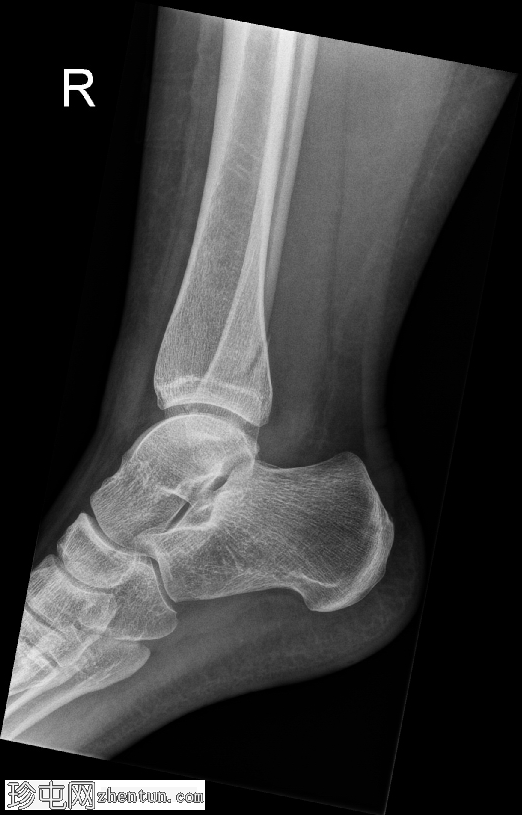

正位片

腓骨远端在胫腓联合水平处发生螺旋形骨折,符合Weber B型骨折。远端骨折块轻度向外侧移位。距骨在踝关节内也出现向外侧移位。

内侧胫距关节间隙增宽,胫腓骨重叠减少,胫腓间隙增宽。这些发现提示胫腓联合韧带损伤,并提示踝关节不稳。可见轻度软组织肿胀。

病例讨论

这种损伤模式符合Weber B型骨折,是由旋后足受到外旋力所致。骨折发生在胫腓联合处,即连接胫骨和腓骨的韧带群。本例中,踝关节内侧以及胫腓骨之间的间隙增宽,提示这些稳定韧带已受力或撕裂。因此,距骨略微外移,表明踝关节不再处于正常对位,且不稳定。

当踝关节失去这种稳定的对位时,关节无法正常承受重量,若不及时治疗,可能导致疼痛、持续不稳定以及关节早期磨损。由于这种不稳定性,此类骨折通常采用手术固定治疗,以重新对位并固定踝穴,从而确保骨折愈合,并降低长期并发症的风险。

患者已用膝下硬石膏固定,并转诊至骨科团队进行切开复位内固定术。